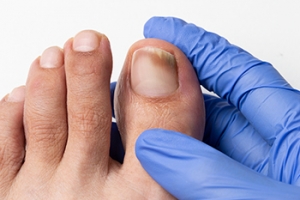

Toenail fungus is a common condition that often begins quietly. You may first notice a small white or yellow spot under the nail. Over time, the nail can become thick, brittle, discolored, and difficult to trim. Some nails may lift from the nail bed or develop a crumbly texture. Warm, moist environments inside shoes create an ideal setting for fungal growth. People who use public pools, share nail tools, or have diabetes are at higher risk. Treatment depends on the severity of the infection. Mild cases may respond to prescription topical medications applied daily. More advanced infections often require oral antifungal medicine to reach the fungus beneath the nail. In certain situations, partial nail removal may be recommended to allow better healing. Early care improves the chance of clearing the infection and preventing spread to other nails. If you notice persistent toenail changes, it is suggested that you see a podiatrist for a proper diagnosis and appropriate treatment.

Treating Toenail Fungus

Fungal infection of the toenail, or onychomycosis, typically appears as a gradual change in a toenail’s texture and color that involves brittleness and darkening. The fungal infection itself occurs beneath the surface of the nail. Aside from discoloration, other symptoms include the collection of debris beneath the nail plate, white marks on the nail plate, and a foul odor emanating from the nail. If ignored, the infection can spread into other nails and the skin; in severe cases, it can hinder one’s ability to work or walk.

Fungal nail treatment may vary between patients and the severity of the condition. Your podiatrist may suggest a daily routine of cleansing that spans over a period of time to ease mild infections. Over-the-counter or prescription antifungal agents may also be prescribed, including topical and/or oral medications. Debridement, or the removal of diseased nail matter and debris, may also be performed. In more severe cases, surgical treatment may be needed. In some instances, the temporary removal of the fungal nail allows for the direct application of a topical antifungal to the nail bed. In other cases, a chronically painful fungal nail that has not responded to other treatments may be permanently removed; this allows the infection to be cured and avoids the growth of a deformed nail.